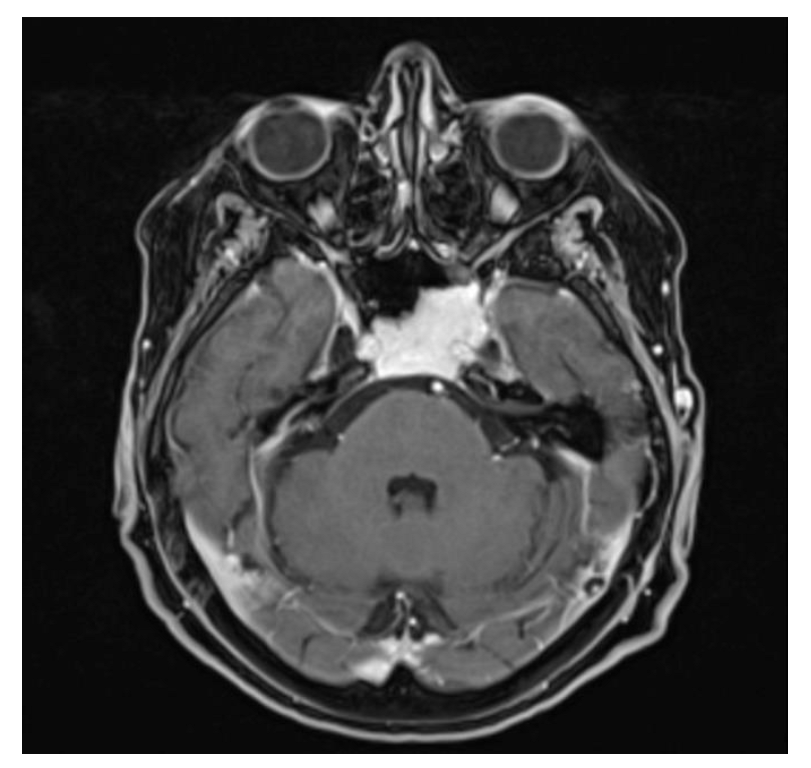

3.2. Case 2—Ecchordosis Physaliphora

| 2 | 69 | F | Cephalea, aqueous rhinorrhea | EEA | Resection and CSF leak repair | Ecchordosis physaliphora | None | None | 24 months | Alive without disease |